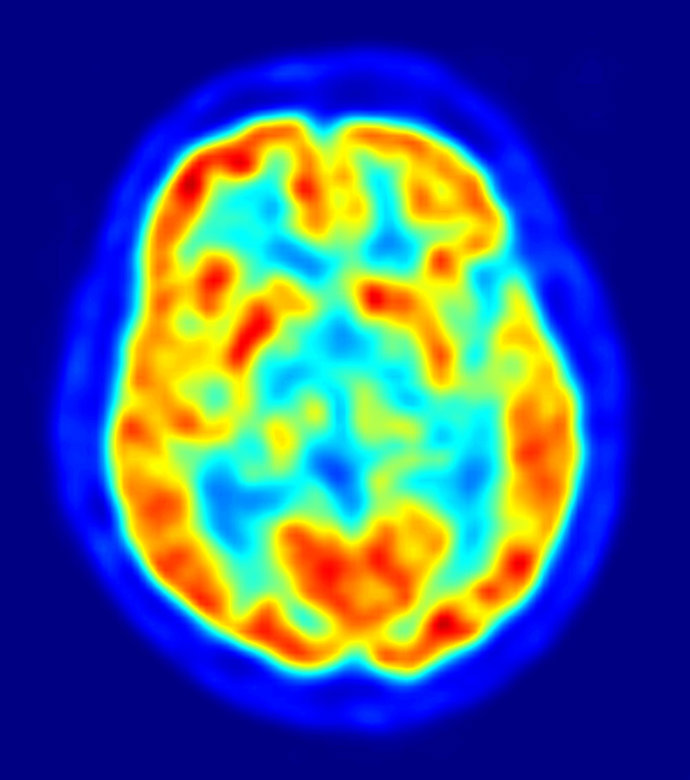

La cocaína cambia el cerebro

El consumo frecuente de cocaína desencadena cambios duraderos en genes que se expresan en una región del cerebro asociada con la recompensa, según un estudio de la Escuela de Medicina del Monte Sinaí en Nueva York (Estados Unidos). El trabajo se publica en la edición digital de la revista 'Proceedings of the National Academy of Sciences' (PNAS).

Los investigadores, dirigidos por Ian Maze, sugieren que estos cambios genéticos podrían influir en los cambios de conducta persistentes que se observan en los adictos a la cocaína.

Los autores examinaron marcadores genéticos, llamados marcadores de metilación de histonas o H3K9me3, que son responsables del silenciamiento de la expresión de regiones de ADN entre los genes. Los ratones expuestos de forma repetida a la cocaína expresaban menos marcadores H3K9me3 que los no expuestos y el efecto persistía incluso después de que los ratones se hubieran abstenido de la cocaína durante una semana.

Después del consumo de cocaína, sin embargo, el número de marcadores descubierto en los ratones disminuía y los autores indicaron que algunas de las regiones de ADN anteriormente silentes en el centro de recompensa del cerebro, el núcleo accumbens, se volvían activas.

Los autores subrayan que se necesitan más investigaciones para determinar si las regiones activadas de ADN influyen en el funcionamiento neural del núcleo accumbens y si causan directamente la conducta adictiva.